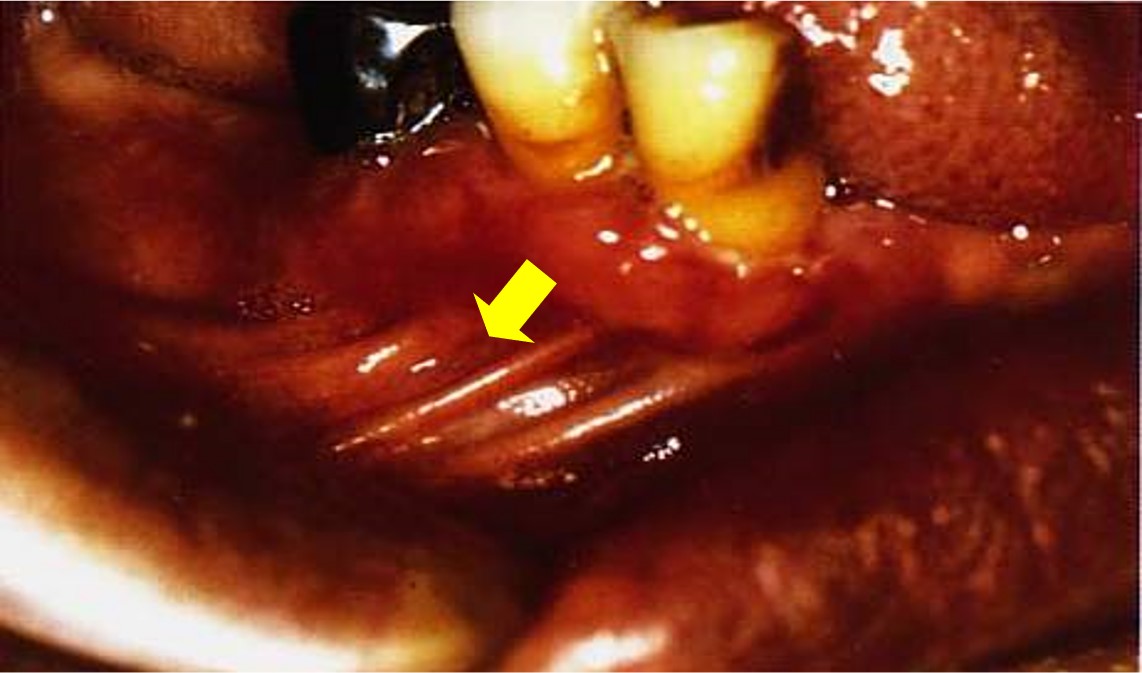

好发于50岁以上老人牙龈(图11.3-4);

图11.3-4 类天疱疮(牙龈)

疱壁较厚,色白,无周缘扩散,面不扩大,不侵犯口唇。